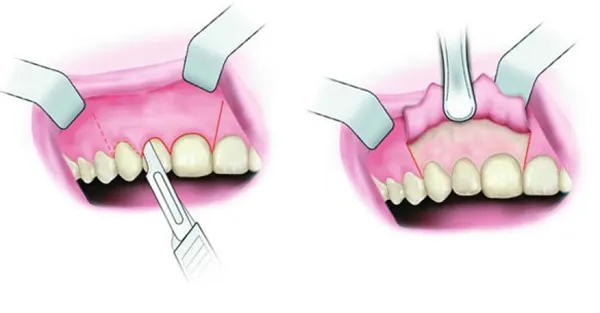

Lợi trùm là một hiện tượng phổ biến trong nha khoa hay xảy ra khi răng khôn mọc bất chợt. Ngoài khó chịu do răng khôn mọc